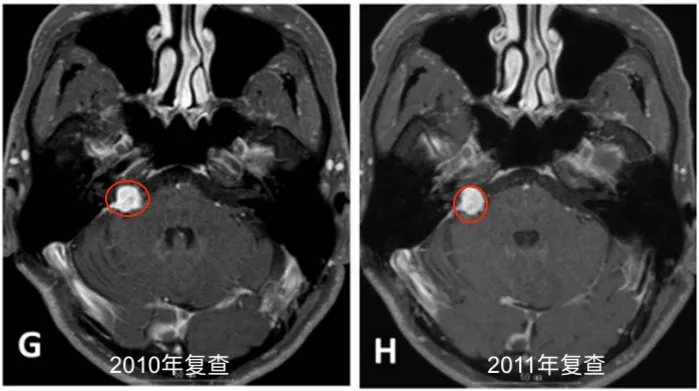

此后,他坚持每六个月复查一次。影像资料(图1 E-J)记录了数年间的随访情况。

2013年底至2014年初:复查显示肿瘤再次开始生长。